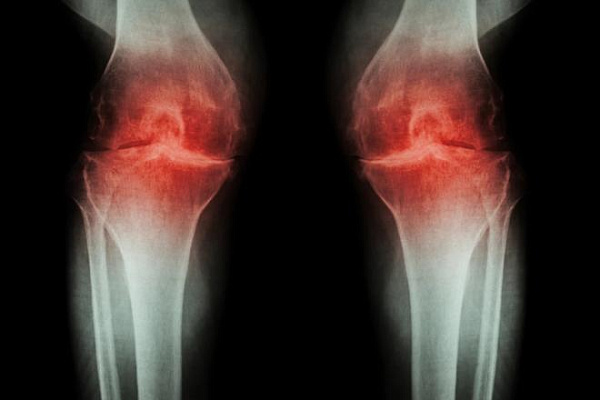

Суставной хрящ — это мягкая амортизирующая ткань, которая находится между костями. По мере изнашивания или из-за повреждения могут развиться постоянная боль и воспаление, что приводит к артриту и другим заболеваниям суставов.

В новом исследовании ученые попытались определить эффективность метода, называемого микропереломом. Процесс лечения включает в себя просверливание крошечных отверстий на поверхности сустава, что стимулирует скелетные стволовые клетки сустава создавать новую ткань. Микротрещины приводят к образованию так называемого фиброзного хряща, который больше похож на рубцовую ткань, нежели на естественный хрящ. Он покрывает кость, но не обладает упругостью и эластичностью, и сравнительно быстро разрушается.

В экспериментах на мышах ученые использовали молекулу, называемую костным морфогенетическим белком два (КМБ2), чтобы мотивировать образование новой кости после процедуры микроперелома. Но прежде, чем этот процесс полностью завершился, они остановили его в нужное время, заблокировав молекулу, называемую фактором роста эндотелия сосудов (VEGF). И это сработало.

«В итоге мы получили хрящ, который состоит из клеток того же типа, что и естественная ткань, и имеет сопоставимые механические свойства, — говорит автор исследования. — Выращенный хрящ восстановил подвижность мышей с остеоартритом и значительно уменьшил боль».